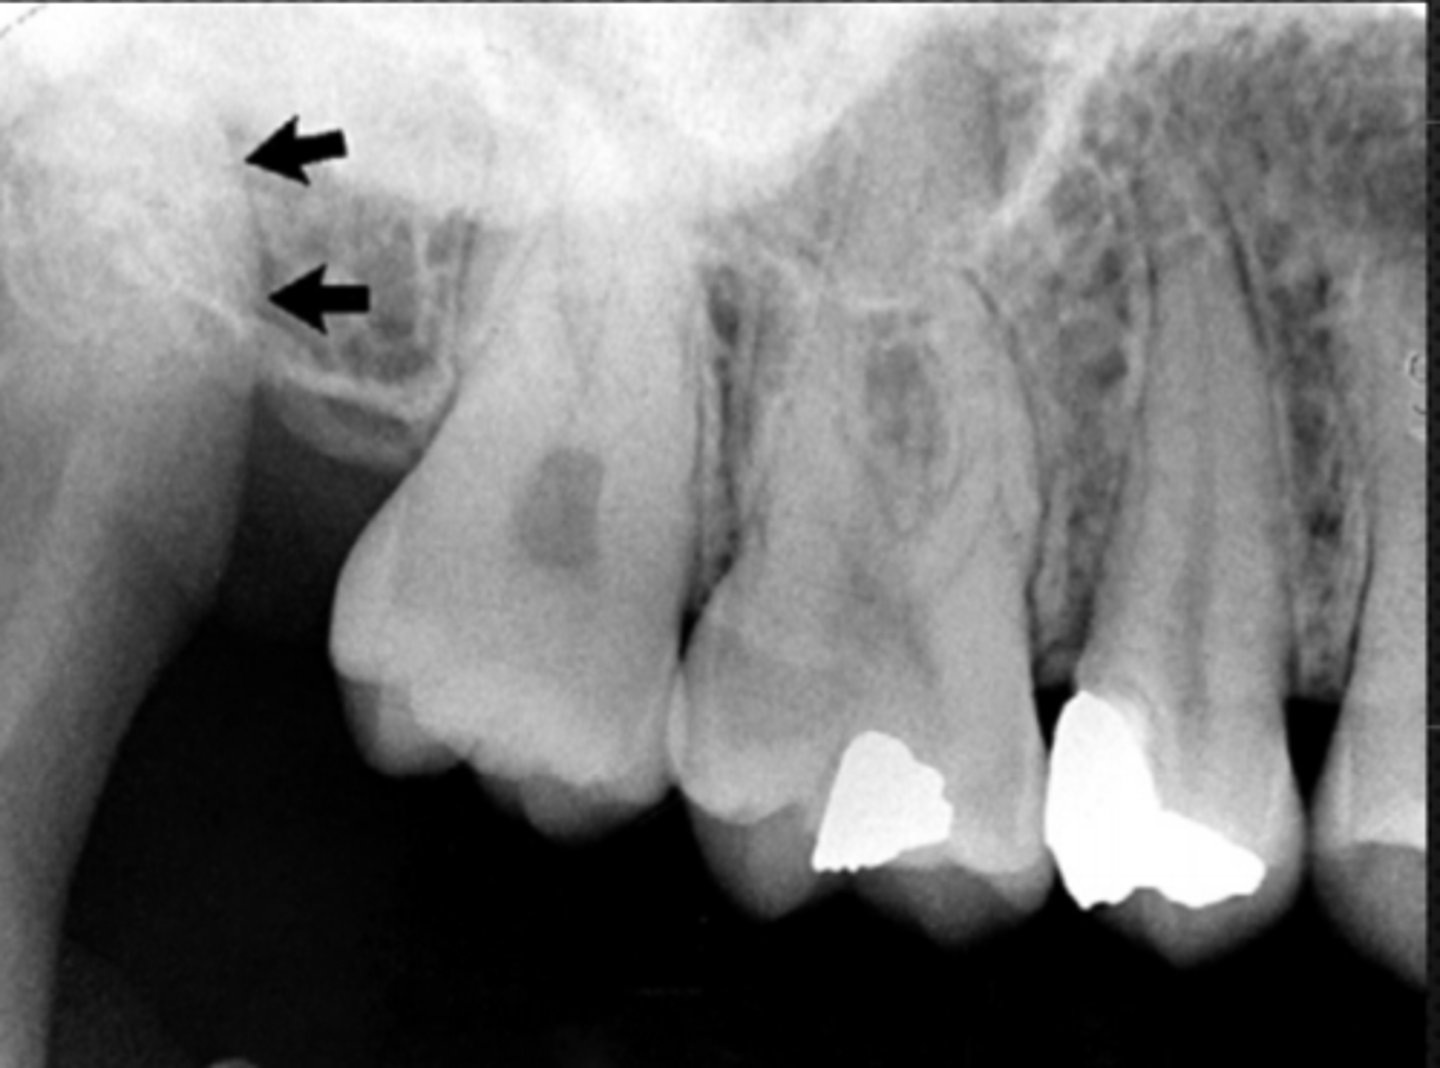

White arrow- nasal conchae

Identify both structures

<p>Identify both structures</p>